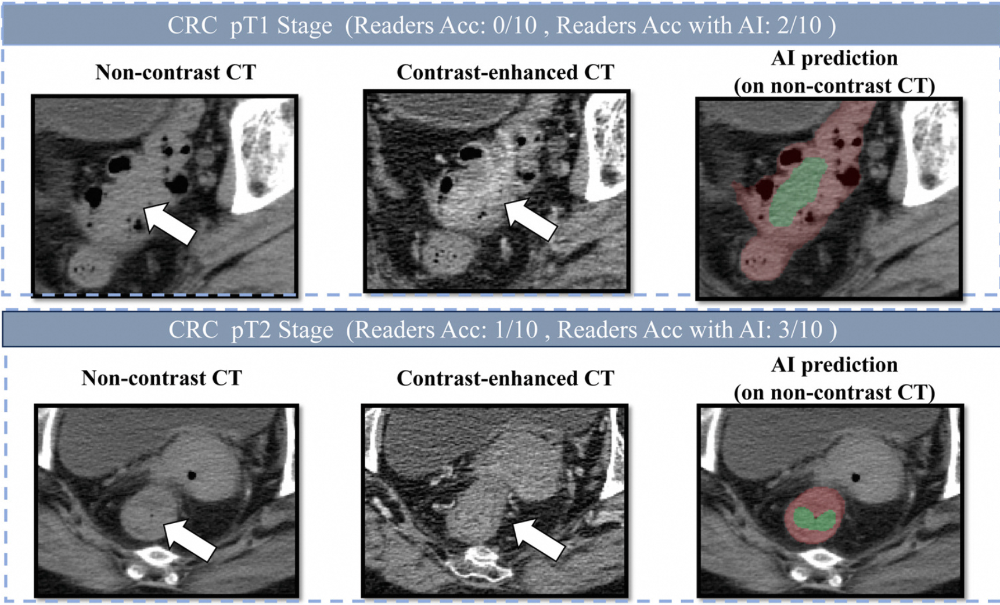

2023年,一位患者在医院拍了一张腹部CT,报告未提及有任何肠道异常。直到2024年被确诊为肠癌时,回溯当初那张CT,才发现癌灶其实早已存在。类似的悲剧并不少见。肠癌是全球第三大高发恶性肿瘤,但早期的筛查检出率长期偏低。研究显示,既往有超过七成的肠癌相关死亡,都发生在未能及时发现的患者身上。如今,由中国科学家开发的一个AI模型,正在试图改变这件事。4月21日,阿里巴巴达摩院联合广东省人民医院、广州市第一人民医院等机构在《肿瘤学年鉴》发文,通过自主研发的AI模型COCA,全球首次证明:仅凭一张普通的平扫CT,就能实现大规模结直肠癌筛查,敏感性86.6%,特异性99.8%。据了解,这是达摩院继胰腺癌模型PANDA、胃癌模型GRAPE之后,在“平扫CT+AI”路线上的又一突破。目前,团队已构建覆盖消化系统多个高发癌种的AI筛查体系,正向“一张CT、筛多种癌”的目标推进。在上海交通大学医学院附属新华医院,结直肠肛门外科副主任医师吴庭玉经常会在门诊碰到让他惋惜的肠癌患者。结直肠癌也被称为“懒癌”。从肠道息肉开始,发展成恶性肿瘤通常需要5到10年,如果在这个窗口期内发现并干预,早期患者的手术治愈率超过90%。“但实际临床中,出现便血征兆后,很多患者以为只是痔疮,并不重视。等到肿瘤进一步增大,发展成肠梗阻,甚至出现肝肺转移才想到来医院检查。此时,治疗已经变得非常棘手,有些人甚至需要进行肠造口。”吴庭玉表示。根据国家癌症中心的数据,2022年,我国新发结直肠癌约51.71万例,死亡约24万人,超越胃癌成为中国第二大高发癌症。另有研究显示,超过七成的结直肠癌相关死亡,都发生在未能及时筛查的人群中。吴庭玉介绍,目前,结直肠癌最常用的筛查手段是社区粪便隐血筛查,如果阳性,则进一步推荐来医院做“金标准”的肠镜检查。“但即使在上海这样医疗资源相对充裕的城市,社区粪便初筛覆盖率超过60%,重点人群的肠镜检查率也只有约30%–40%。”“此外,粪便隐血检测敏感性较高,但特异性不足,需要再通过肠镜最终确诊。但做肠镜需要提前预约、服泻药清肠、过程有创且不适,很多人因此一拖再拖。”吴庭玉表示,从粪便初筛阳性到进一步接受肠镜检查,转化率仍然有限。达摩院资深算法专家、多癌筛查技术负责人张灵告诉“医学界”,大约在2022年,团队关注到了肠癌。“那时,我们刚在胰腺癌的‘平扫CT+AI’筛查上取得突破。我们也开始思考,肠癌的早筛困境,是不是也能通过这种方法得到解决?”要知道,中国各级医院每年要完成数千万次腹部和胸部CT扫描,这些影像中也记录有结直肠的轮廓。如果能直接“二次利用”,就能在不增加任何负担的情况下,实现对结直肠癌的大规模筛查“平扫CT的对比度较低,肉眼极难辨认早期的肠癌病灶,但这恰恰是AI可以发挥优势的地方。”张灵表示,在和不少临床专家详细沟通后,团队进一步坚定了这一想法,并正式启动了COCA肠癌筛查模型的研发。从医学的角度,开发基于“平扫CT+AI”的肠癌筛查系统,存在不小的挑战。张灵告诉“医学界”,肠癌CT筛查的独特挑战,一方面是结直肠的范围太大了,几乎横跨了整个腹部,弯弯绕绕,平扫CT中关于肠道结构的识别和检测分割,本身就是一大难题。另一方面,患者日常做平扫CT,并不会进行肠道准备,他们的肠腔内充满各种内容物,影像表现极其复杂。而肠道肿瘤的形状也没有规律,什么形态都有可能,进一步增加了鉴别的难度。张灵表示,针对一系列难题,团队采用了“定位+诊断”的双阶段框架:先通过AI定位结直肠区域,再在定位范围内检测肿瘤。同时,针对直径小于3厘米的肿瘤,团队还引入专门的训练模型,使得AI能精细分割形态复杂的肠道部位,并克服内容物干扰,提高了对小病灶的检出能力。经过三四年的研发,COCA模型的成果最终问世。根据此次发布在《肿瘤学年鉴》的研究结果,在六个国际中心,涵盖2053例患者的验证中,COCA的AUC(衡量整体判别能力的指标)达到0.967至0.996。与10名放射科医师的CT对照阅片研究显示,COCA的肠癌检出敏感度,比医生平均水平高出20.4%,特异度高出5.4%。当医生在AI辅助下重新阅片,其诊断准确率显著提升——一位经验丰富的普通放射科医师,准确率从75.6%跃升至90.3%。不仅仅是腹部CT。张灵告诉“医学界”,在临床中,胸部CT的使用量往往更大,但其图像通常只覆盖少部分肠道区域。而即便如此,若肠癌在胸部CT扫描范围内,COCA识别敏感度仍达到81.8%,特异度99.9%。这意味着,一个可能只是来做肺结节检查的患者,也有机会“顺带”完成肠癌筛查。更进一步,研究团队开展了两轮大规模真实世界回顾性验证,覆盖27433名连续就诊患者。结果显示,COCA保持了86.6%的敏感性和99.8%的特异性,并从中识别出5例此前被临床漏诊的肠癌。其中有一名患者,此前已连续两年进行过平扫CT检查,但后来才通过肠镜确诊肠癌,此时肿瘤已出现进一步发展。而若当时就有COCA介入,这两年间的任何一张CT,都可能成为发现肿瘤的契机。值得一提的是,面对不同人群,COCA还准备了两个版本——“高特异度”和“高灵敏度”。高特异度指的是阳性误报率低,适用于全人群的大规模肠癌筛查。“大部分人是健康的,如果出现太多假阳性,不仅会引起公众的恐慌,也会给医疗系统增加不必要的负担。”张灵说。高灵敏度版本则面向数量有限的高风险人群,其核心是追求尽可能不漏诊。研究结果显示,COCA高灵敏度版本,对I期肠癌的检出率达到83%至92%,甚至能检出尚未癌变的进展期腺瘤,其检出能力优于目前文献报道的其他技术路线。据张灵介绍,目前,COCA模型可以无缝嵌入临床医生的工作流,“它能在后台对CT影像进行自动筛查,一旦发现可疑病灶立刻发出提示,并标注出疑似肿瘤的位置、大小及概率,提醒医生进行详细的评估。”事实上,这已经不是达摩院团队第一次在“平扫CT+AI”的技术路线上取得突破。2023年,团队率先发布了胰腺癌早筛模型PANDA,登上《自然·医学》,后获得了美国FDA的“突破性医疗器械”认定。《自然·医学》同期发布评论文章题为:基于影像AI的癌症筛查即将进入黄金时代。2025年6月,全球首个胃癌影像筛查AI模型GRAPE再次发表于《自然·医学》。它瞄准了胃镜在中国普及率不高的短板,首次利用平扫CT在大规模多中心研究中发现了多例漏诊胃癌患者。如今COCA的发布,意味着达摩院团队“平扫CT+AI”的技术路线,已经在多个高发癌种上得到了系统验证。事实上,目前国际上最火热的多癌筛查研发赛道是“液体活检”。它瞄准血液检测,希望通过分析血液中的肿瘤标志物,来一次性实现多癌筛查。“最开始,我们一定程度上也受到了液体活检的启发。”张灵告诉“医学界”,“但它终归需要患者去主动抽血,专门做检查。平扫CT不同,它在我国的日常用量非常大,这些图像本身就在后台,我们只需要用AI跑一下。”此外,目前国际上最主流的液体活检多癌筛查产品,单次检测费用约为1000美元。“而结合平扫CT的AI诊断策略,不需要额外检查、不产生额外费用,甚至不需要患者主动配合。”张灵表示。而站在更宏观的公共卫生视角,这一技术路线的意义则更为深远。尤其是在基层,张灵表示,如今,中国有大量基层医院配备了CT设备,但仍缺乏足够的专科医生来系统性阅片。如果AI能先行筛查,就相当于给基层配备了一位“癌症检测专家”,提示高风险的第一时间转诊至上级医院,大量患者也将从中获益。据张灵介绍,除了胰腺癌、胃癌、肠癌,团队还在同步推进食管癌、肝癌诊断工具的开发,并希望最终能将“消化系统五癌”整合为联合筛查系统。“同时,我们在乳腺癌、肾癌等癌种上的研发也取得了阶段性的进展。”张灵表示,“我们的最终目标,是希望只要患者做了CT,不管胸部还是腹部,系统都能把里面的癌症筛查出来,让多数癌症患者,都能在早期得到及时的治疗。”